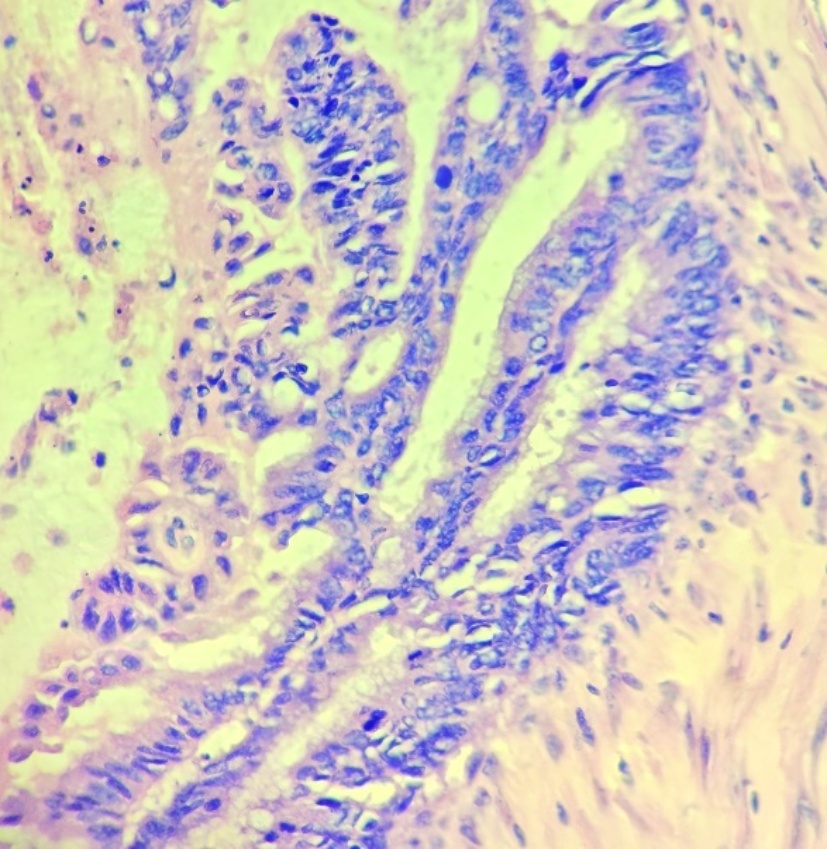

患者阑尾未见明确显示,相应区短条状高密度影,周围条片及淋巴结影,边欠清,部分轻度强化征象,局部肠壁模糊,右下腹肠系膜及大网膜条片影,边欠清。区段小肠肠壁明显增厚,考虑肿瘤可能性大(见图4(a)图4(b))。经多学科讨论后,考虑患者阑尾肿瘤合并小肠肿瘤可能性大,各项术前检查未见明显转移征象,建议再次行手术探查。术中见:肝周及盆底血性积液,量约100 ml,部分小肠黏连与腹壁原切口下方,顿性分离黏连肠管,部分小肠、大网膜黏连固定于右下腹回盲部,松解黏连后,见回盲部、临近小肠系膜、大网膜及右侧腹壁触及质硬结节,距回盲部2 m处小肠肠管明显增粗、质硬,肝脏表面光滑,无明显占位。给予切除距回盲部远端10 cm升结肠及近端10 cm回肠,行回肠及升结肠吻合。切除距回盲部2 m处病变小肠,行小肠吻合。术后病理示:(距回盲部2 m处小肠):黏液癌(隆起型,3 × 2 cm),肿瘤侵透浆膜,脉管癌栓(−),神经侵犯(+),两侧手术切缘未见癌累及,肠周淋巴结内未见癌转移(0/2) (见图5图6)。(回盲部小肠):送检小肠组织,黏膜慢性炎,浆膜面及肠系膜内出血、纤维组织及间皮增生并见少许无上皮黏液,两侧切缘未见癌累及,肠周淋巴结内未见癌转移(0/10)。病理分期:pT4bN0Mx。(右半结肠)送检肠管组织,浆膜面见少量异型腺体浸润,意见为癌。周围组织呈异物肉芽肿性炎,两侧手术切缘未见癌累及,肠周淋巴结内未见癌转移(0/21)。(腹膜结节)送检组织内纤维组织结节状增生。(大网膜)网膜组织内见多处纤维组织增生伴异物巨细胞反应。经多学科会诊讨论后,考虑患者诊断原发肿瘤来自小肠,阑尾肿瘤为小肠侵犯所致。术后患者于肿瘤科行3周期Xelox方案化疗:奥沙利铂130 mg/m2,静脉输注2 h,第1天。卡培他滨每次1000 mg/m2,每日2次,第1~14天。患者术后随访至今未见异常。

Figure 5. Postoperative pathology of the appendix (HE×100)

5. 小肠术后病理(HE×100)

Figure 6. Postoperative pathology of the appendix (HE×400)

6. 小肠术后病理(HE×400)